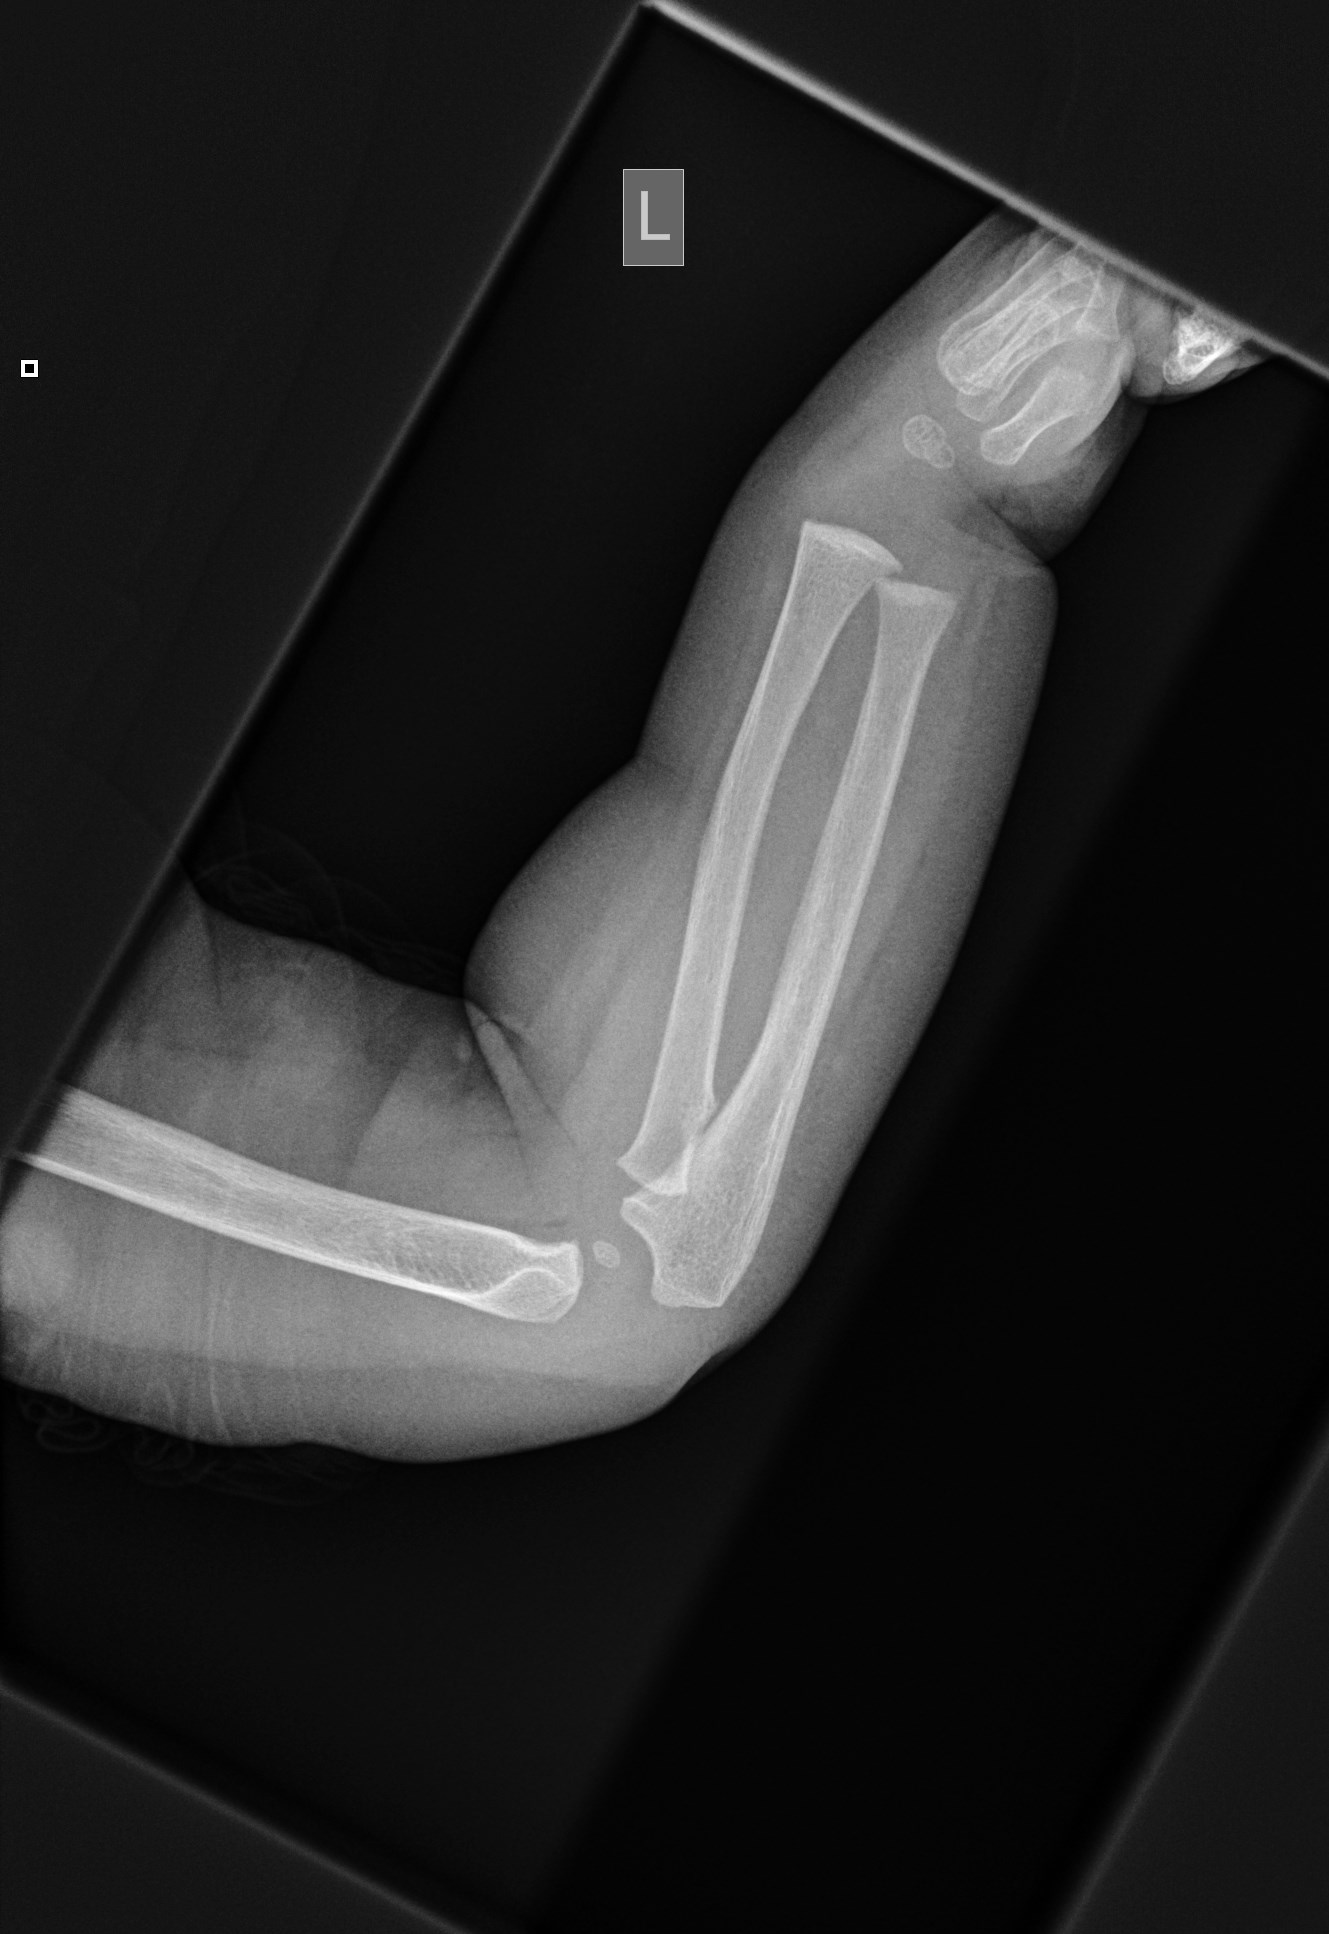

A child xray elbow Lateral, AP view of the forearm caused by bone Forearm X Ray Child Both bone forearm fractures are one of the most common pediatric fractures, estimated around 40% of all pediatric fractures. Reference article, radiopaedia.org (accessed on 18 oct. It was created to provide examples of standard radiographs of. Buckling without a visible fracture line is termed a 'torus' injury. If there is a visible fracture in the cortex on one side with. Forearm X Ray Child.